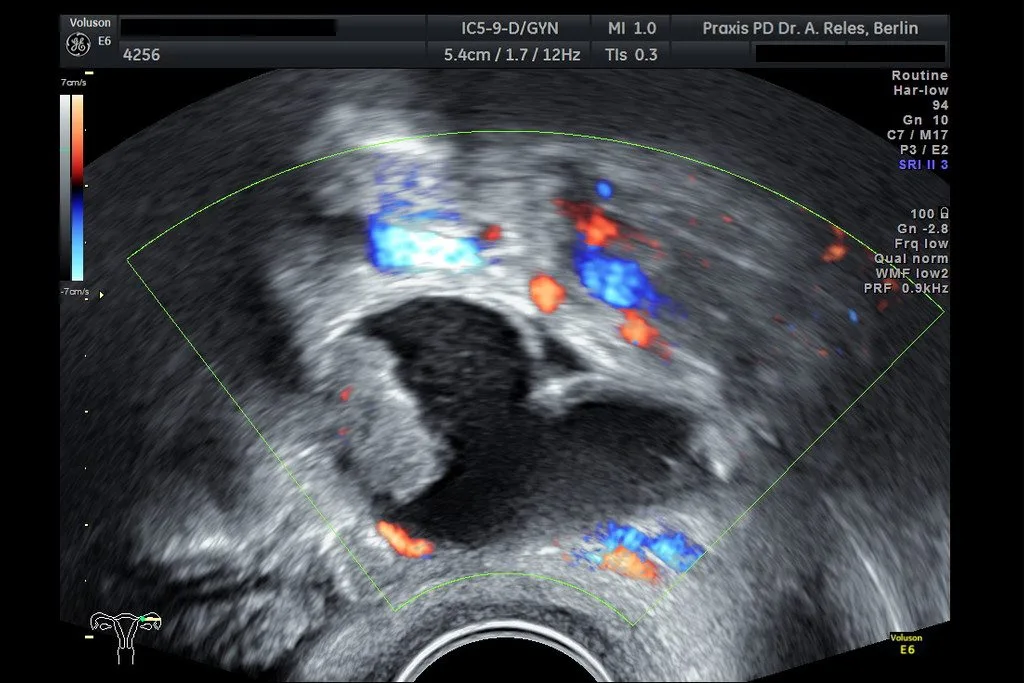

• Farbdoppler-Sonographie

• Diagnostik von Veränderungen an

Gebärmutter und Eierstöcken

• Früherkennung von Tumoren im Genitalbereich